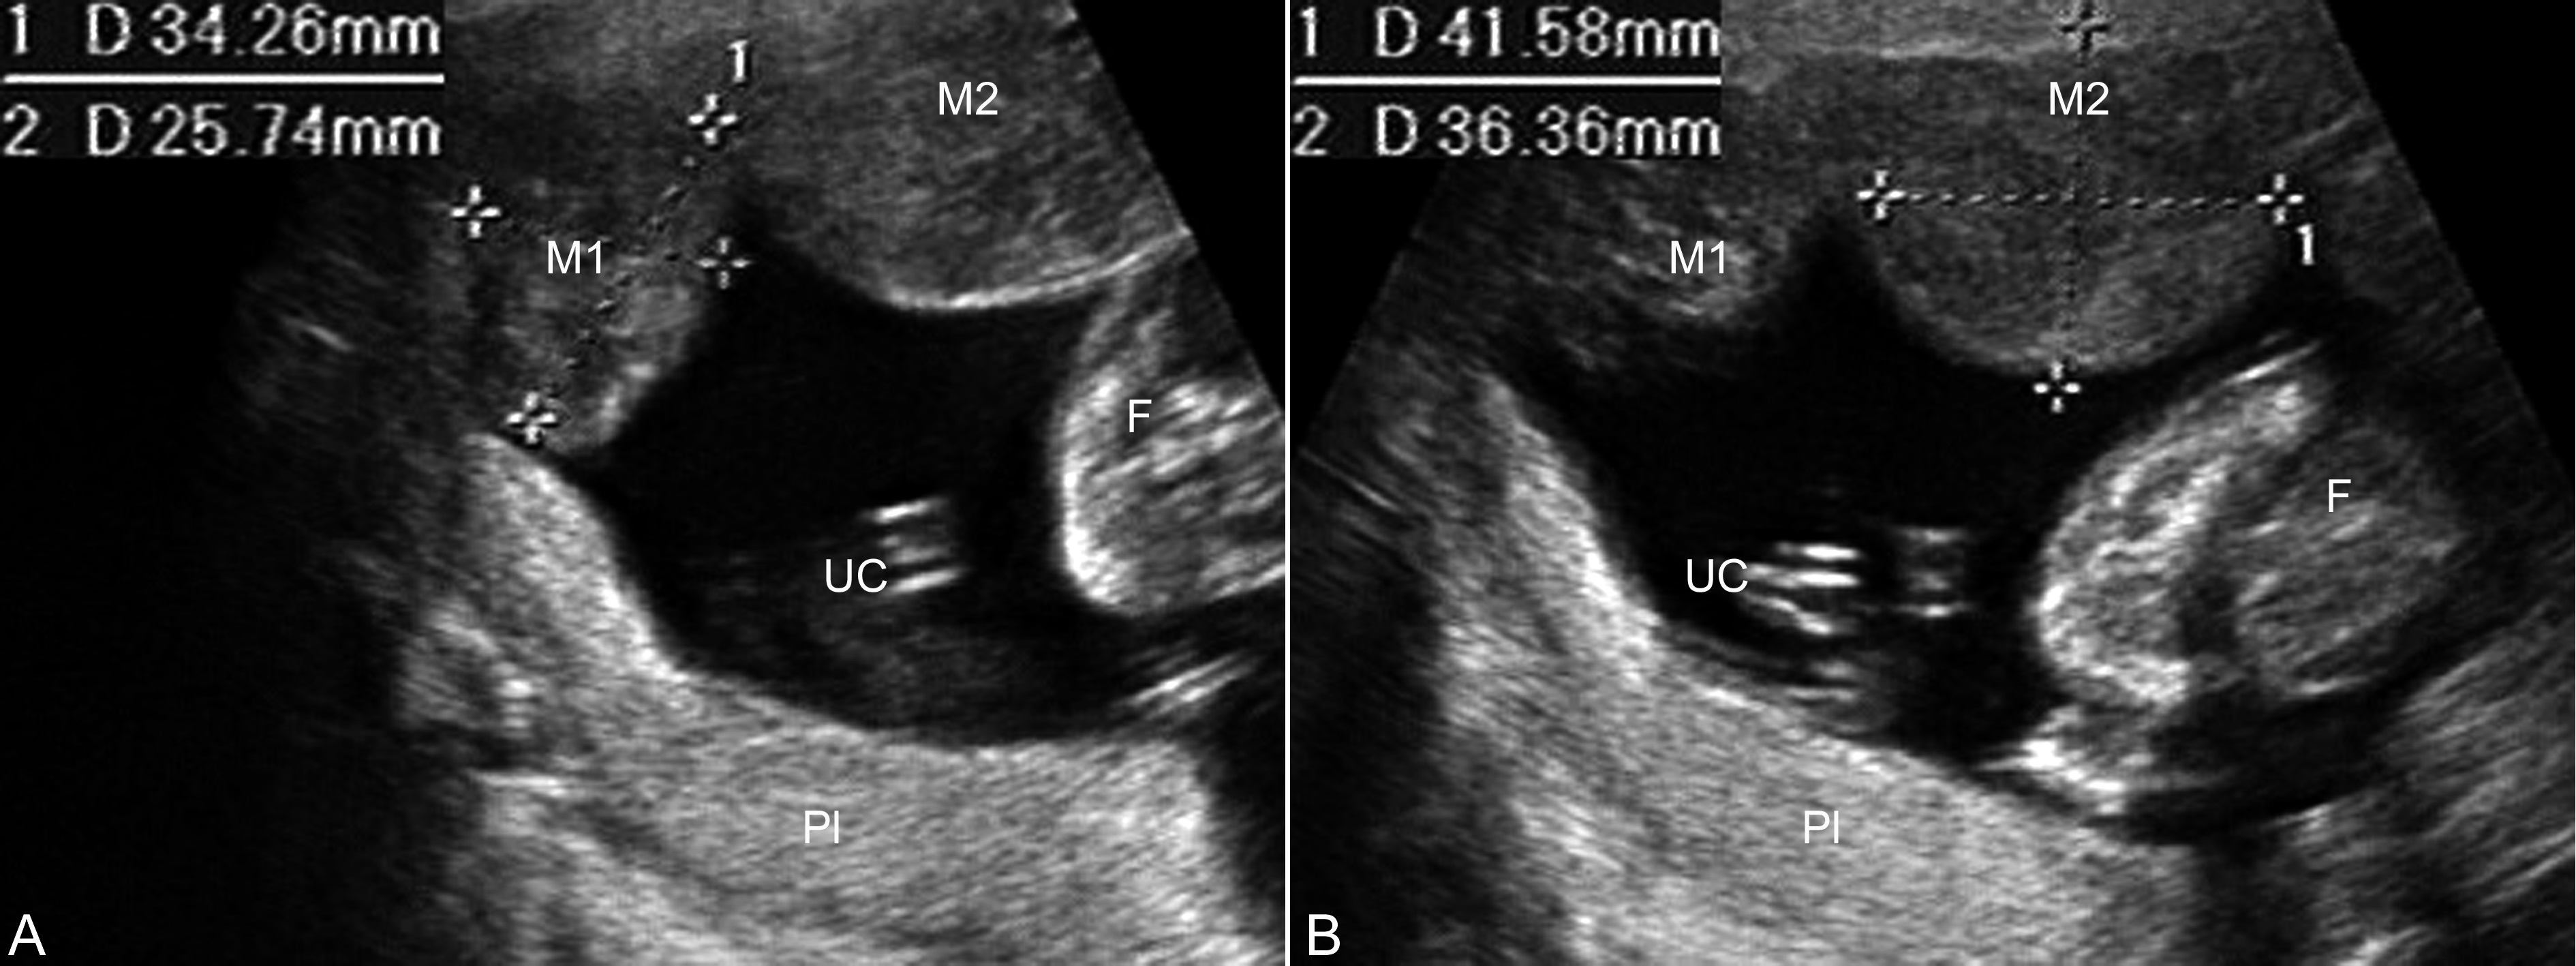

图1妊娠合并子宫肌瘤声像图

子宫前上壁可见两个肌瘤回声,测量大小分别为32mm × 26mm(A,M1)、42mm × 36mm(B,M2),胎盘(Pl)位于子宫后壁

UC:脐带;F:胎体